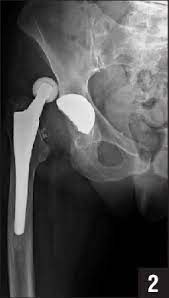

צילומי רנטגן פשוטים יראו פריקה ואת כיוונה (אחורית או קדמית). צילומי רנטגן יכולים לעיתים לרמוז על סיבת הפריקה כגון מיקום לא אופטימלי של המשתלים או שחיקה של הפוליאטילן. לעיתים כשהתמונה לא ברורה ל CT יש תפקיד נוסף במיקום המשתלים.